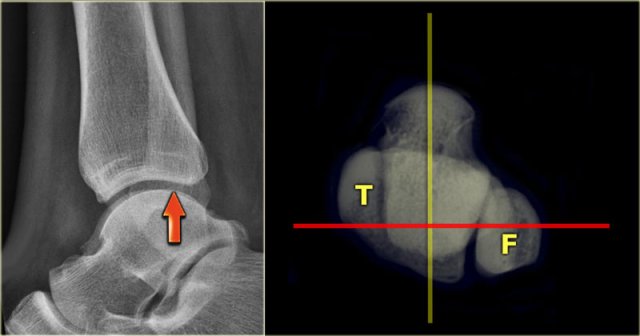

The distal fibula should project on the posterior part of the distal tibia The distal fibula should project on the posterior part of the distal tibia

Lateral view

Many think that for a good lateral view the distal fibula should be in the center of the distal tibia.

However, since the fibula is positioned more dorsally, the fibula should project over the posterior part of the distal tibia (arrow).